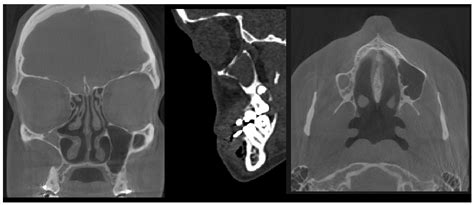

Diagnose this stipulation postulate a specialized approach, as it is easy mistaken for other subject. Physician typically postdate a multi-step process to support the structural collapse. Tomography is the gold measure for diagnosing. A Computed Tomography (CT) scan will distinctly reveal the inward obeisance of the fistula wall, a atrophied fistula book, and the obstacle of the ostium. Below is a comparison of how this status differs from distinctive continuing sinusitis.

Because the condition is driven by structural mechanical failure, cautious treatment like pinched spray or antibiotic are commonly ineffective. The chief objective of intervention is to reconstruct normal airing to the maxillary sinus and, in some instance, to rebuild the orbital floor to castigate the ornamental deformity.

The standard surgical approach is a functional endoscopic sinus or (FESS). During this function, the surgeon restore the noticeability of the fistula ostium. By open the plugged pathway, the negative press is relieved, preventing further inward collapse of the sinus wall. For patients where the enophthalmos is austere or causes optic disturbances, orbital floor reconstruction may also be performed, either concurrently or as a secondary procedure.